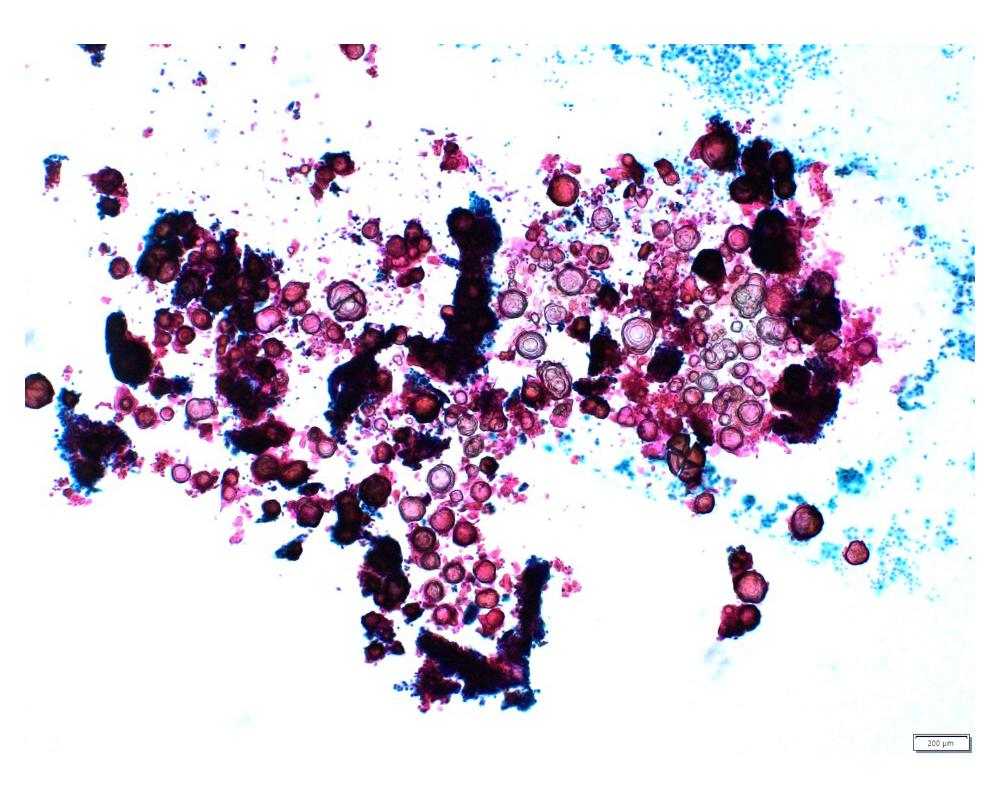

種別:泌尿器

| 年齢 | 68歳 | 性別 | 男性 |

| 採取部位 | 尿 | 採取方法 | 自然尿 |

| 検体処理法 | 従来法 |

既往歴:大腸癌

現病歴:S状結腸癌ならびに肺転移にて化学療法中。2週間前から排尿困難、残尿感があり、泌尿器科に紹介された。直腸診で前立腺は超胡桃大、全体に固く表面やや不整であった。精査のため、まず尿細胞診が行われた。

(画像2、5~8は同一の倍率です)

| 正解 | 1.大腸癌 |